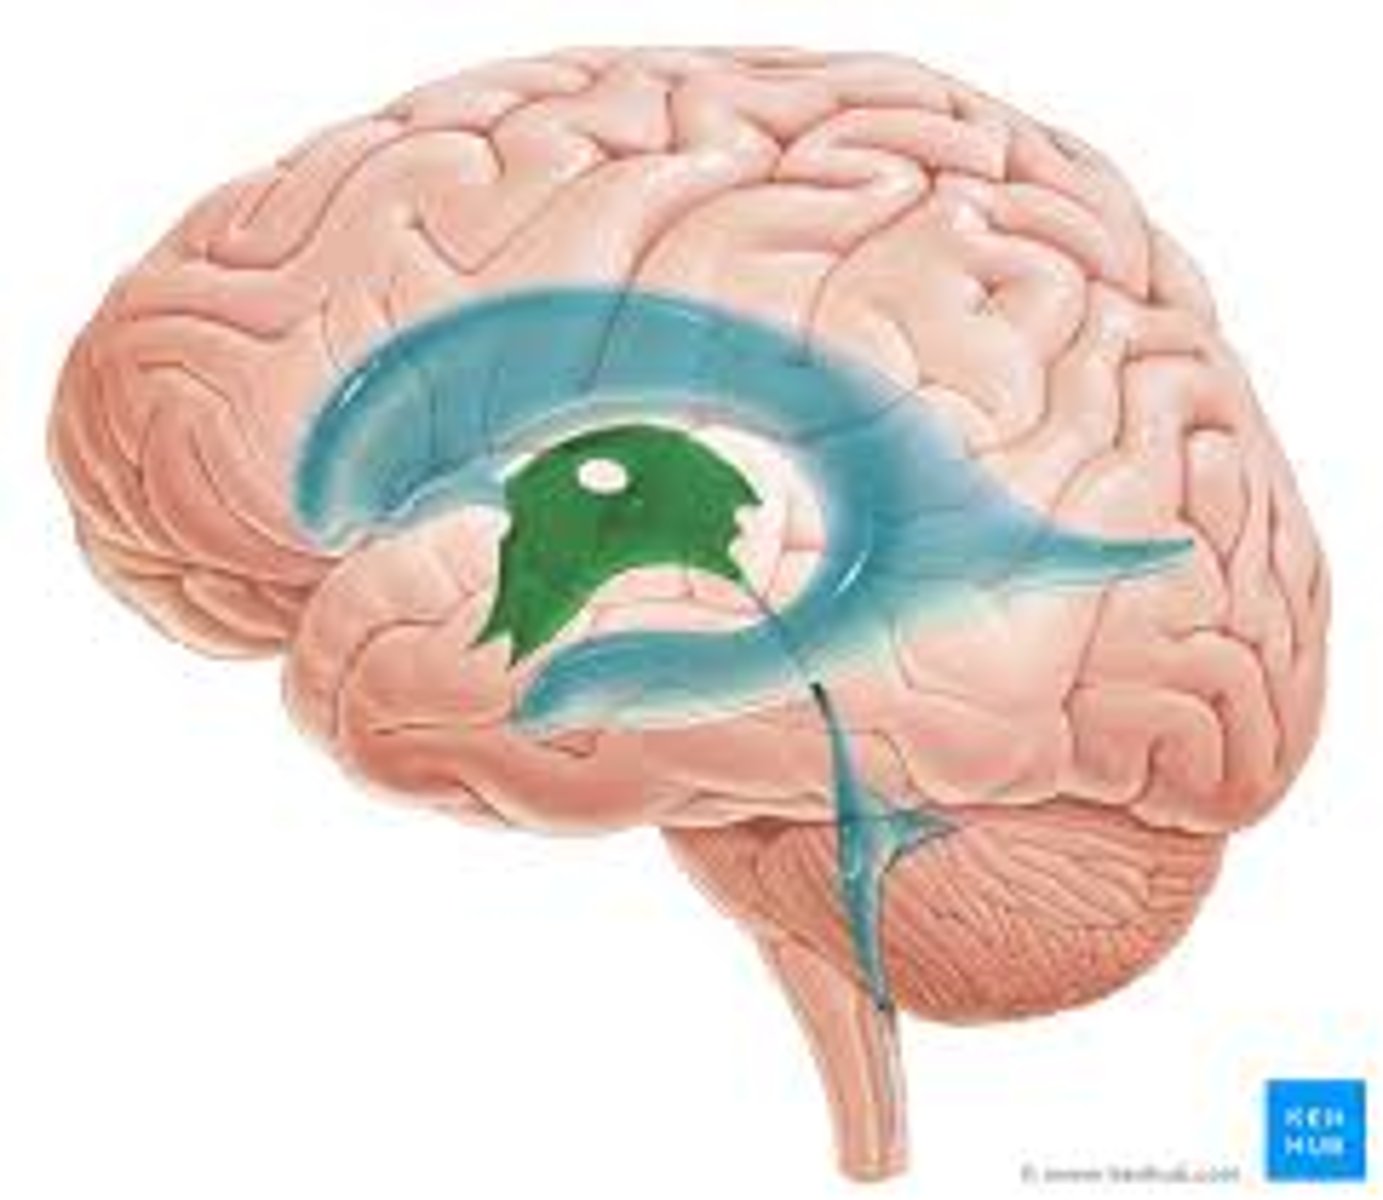

lateral ventricle

third ventricle